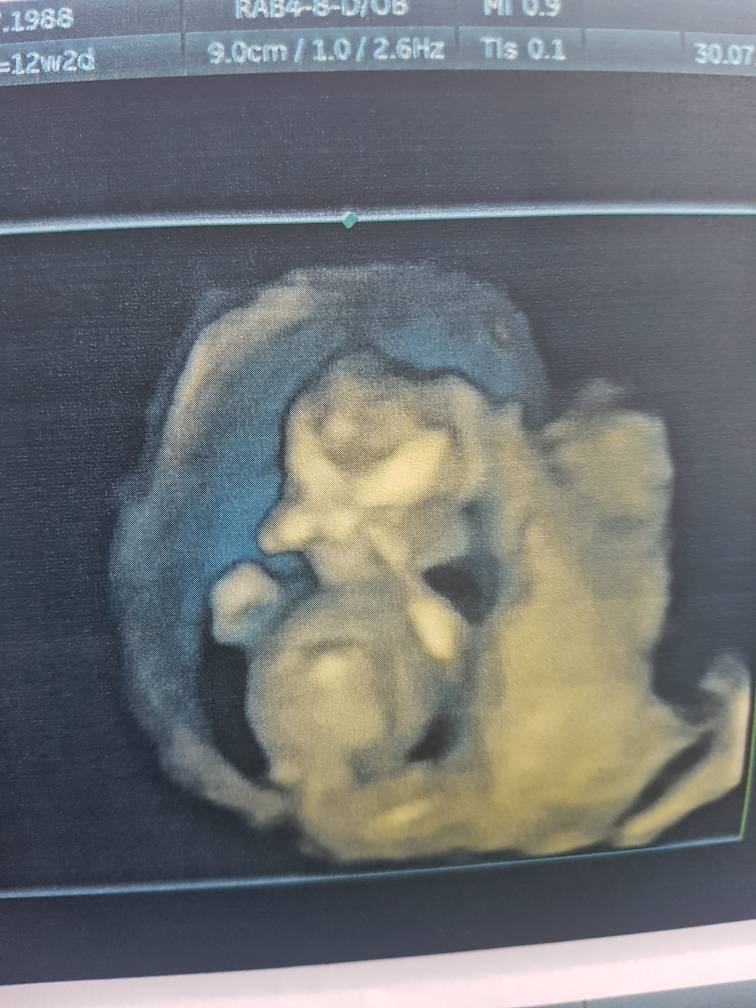

Kochane odzywam się do was po krótkiej przerwie, chciałam wam powiedzieć co u mnie słychać, mialam dziś prenatalne, wszystko jest w porządku, dzidzia fikała, krzyzowała nóżki, zaslaniala rączkami buzke, serduszko bilo jak galopujący konik [emoji4] jestem szczęśliwa i mam nadzieje ze tym razem bedzie już tylko dobrze. Dziś według usg dzidzia ma 12+4 i ma 6 cm [emoji4] jedyne co mnie zaniepokoilo to reakcja doktora na moje siniaki A konkretnie heparyne, powiedział że to skandal że ktoś mi ja przepisał..... bardzo mi to siadlo na głowę... ten doktor pracuje w genetyce.... nie wiem w którym miejscu byłabym teraz bez zastrzykow? Może w tym samym ? A może nie dotarlabym do tego etapu ? Tego się nie dowiem, mam jednak ogromną nadzieję że nie szkodze swojej fasolce.

Aha, bym zapomniała, powiedział że prawdopodobnie to chlopczyk